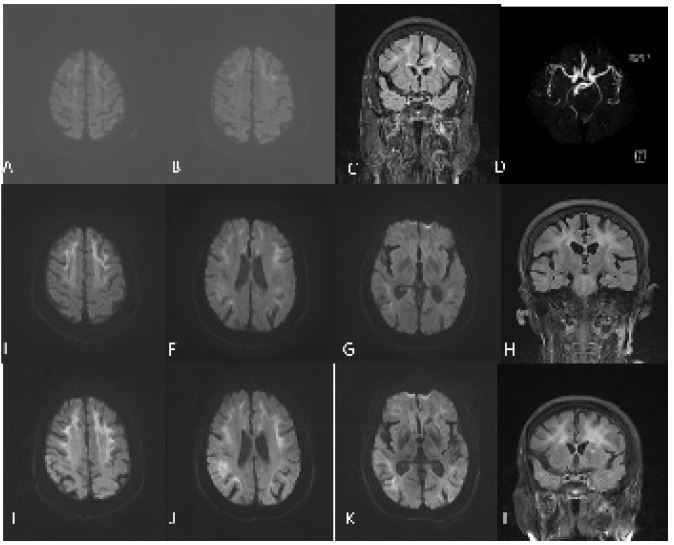

Neurologic examination demonstrated lethargy, comprehensive cognitive decline including memory impairment, execution dysfunction and aphasia. Static and postural tremors of hands and ataxia were noted without obvious muscle weakness. Mini-Mental State Examination was 20 (normal threshold, 24/30), Frontal Assessment Battery score was 12 (normal threshold, 16/18). The results of routine laboratory tests were within normal limits. Urinary tests showed increased white blood cell counts and bacterial counts. Brain MRI showed multiple patchy high-intensity signals in bilateral frontal lobes and left temporal occipital lobe on DWI, while equal signals on apparent diffusion coefficient (ADC). Compared with the previous imaging, the lesion area was significantly enlarged, and DWI high signal were distributed along the corticomedullary junction, similar to the “cockscomb pattern” (Figure 1E-H). Urinary ultrasound showed cystitis. Electroencephalogram showed no epileptic discharge. Nerve conduction study (NCS) showed that latency of F-wave of the left tibial nerve was slightly prolonged. Skin sympathetic response (SSR) showed amplitude decreased in the four extremities and latency prolonged slightly in both lower limbs. A histopathological examination of skin biopsy specimens showed eosinophilic hyaline intranuclear inclusions in the fibroblasts and sweat gland cells of the skin tissue (Figures 2A,2B). He did not test for NOTCH2NLC gene. However, Fragile X associated syndrome (FXTAX) was ruled out since the genetic testing for the fragile X chromosome mental retardation gene 1 (FMR1) revealed no abnormal GGC repeat expansion (Figure 2C). 8 months later, the patient was readmitted with «lung infection, urinary tract infection». During this period, he continued to experience intermittent dizziness and unsteady walking.

Figure 1: Neuroradiological findings. DWI (A,B), FLAIR (C) and MRA (D) reveals no abnormalities. DWI shows multiple patchy high-intensity signals in the corticomedullary junction of the bilateral frontal lobes and left temporal occipital lobe (E,F). FLAIR shows diffuse high-intensity signal of white matter (G). ADC shows equal signals (H). FLAIR, fluid-attenuated inversion recovery; DWI, diffusion-weighted image; MRA, magnetic resonance angiography.

Figure 3: (H) findings. DWI shows multiple strip like high-intensity signals in the corticomedullary junction of the bilateral frontal parietal lobe, corpus callosum, and near the posterior horn of lateral ventricle (A,B). FLAIR shows diffuse high-intensity signal of white matter (C). MRA shows no significant intracranial aortic stenosis or occlusion (D). DWI shows that bilateral subcortical high-intensity signals were enhanced compared to before, and the lesion area was enlarged (E-G). DWI shows the lesion area was enlarged again (I-K).